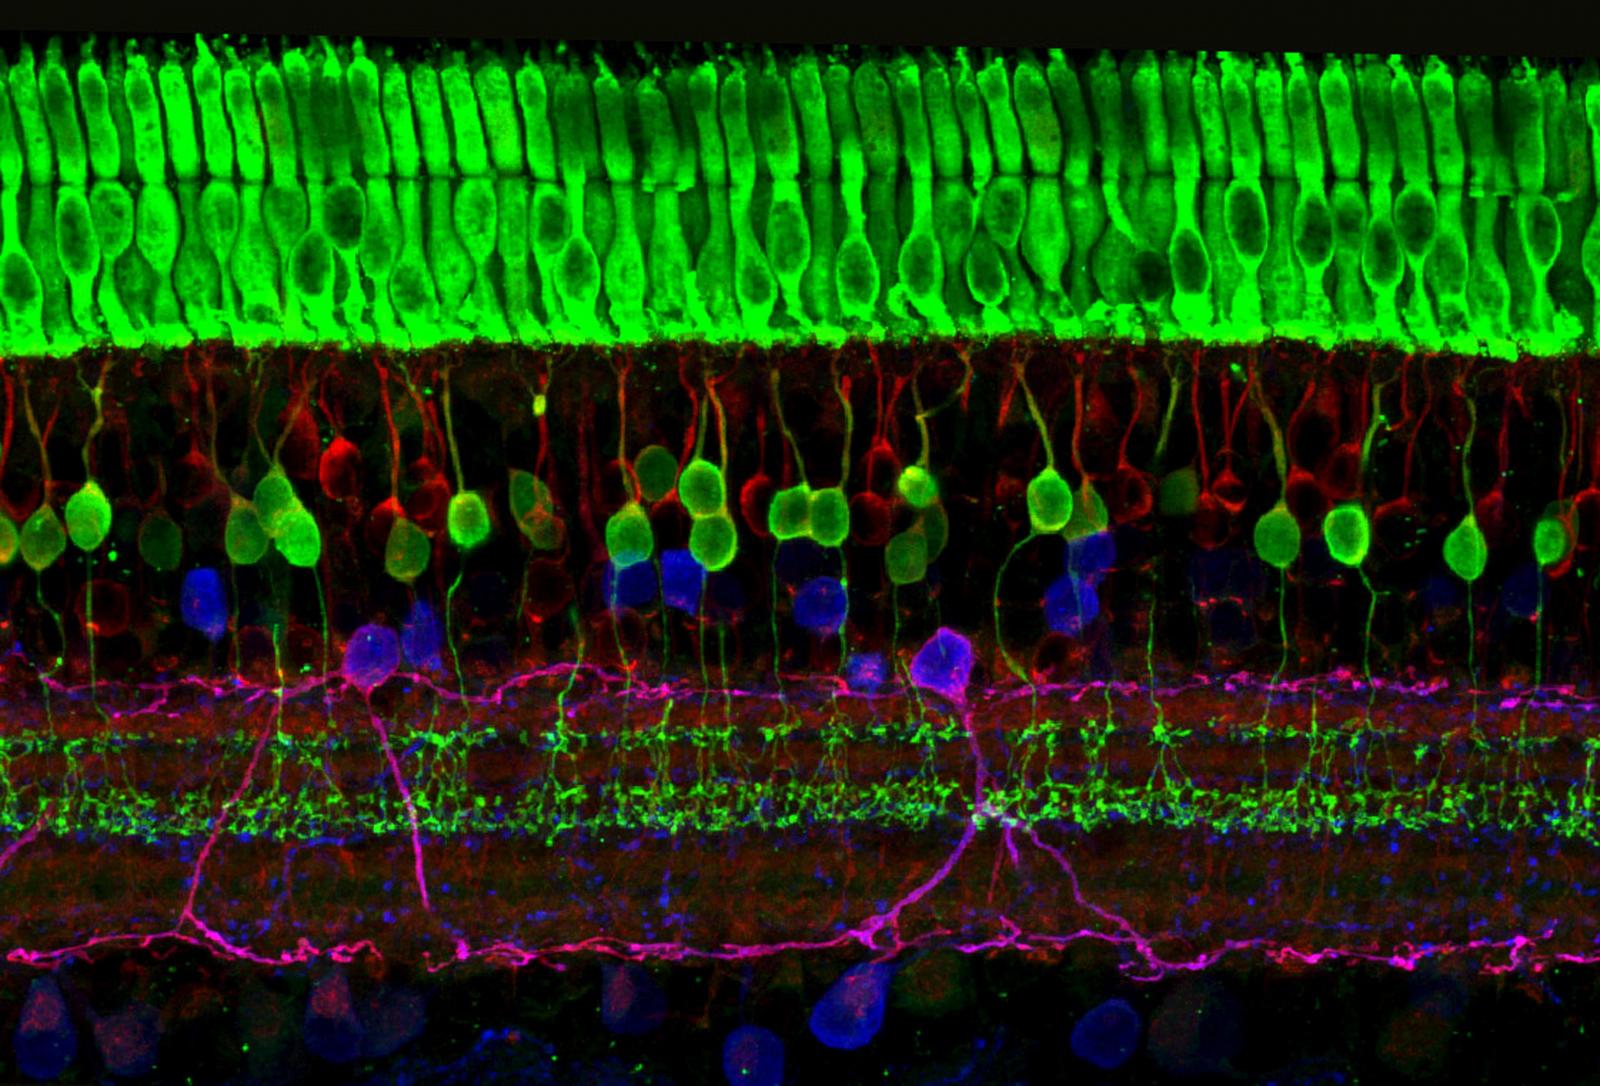

Изображения и анатомия сетчатки глаза

Раздел: Визуальный дайджест